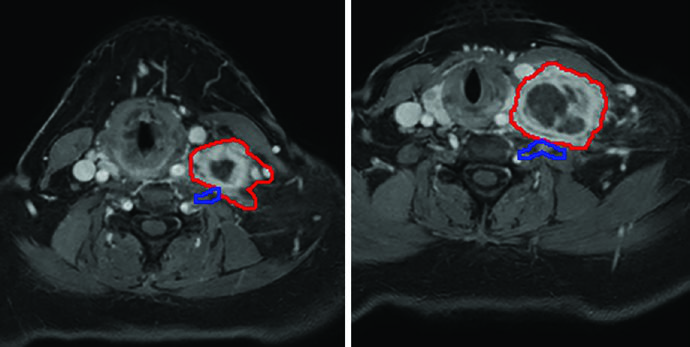

Oligometastatic disease adjacent to brachial plexus. A 55-year-old woman with an unresectable solitary colorectal metastasis to the supraclavicular fossa. The 6-cm node was treated with 45 Gy in 5 fractions, twice weekly. The radiation plan was created with MRI simulation to differentiate the GTV (red) from the brachial plexus (blue) — a crucial differentiation that would be impossible on CT alone given the similar densities of these structures. The mass recurred 3 years later in the left neck.